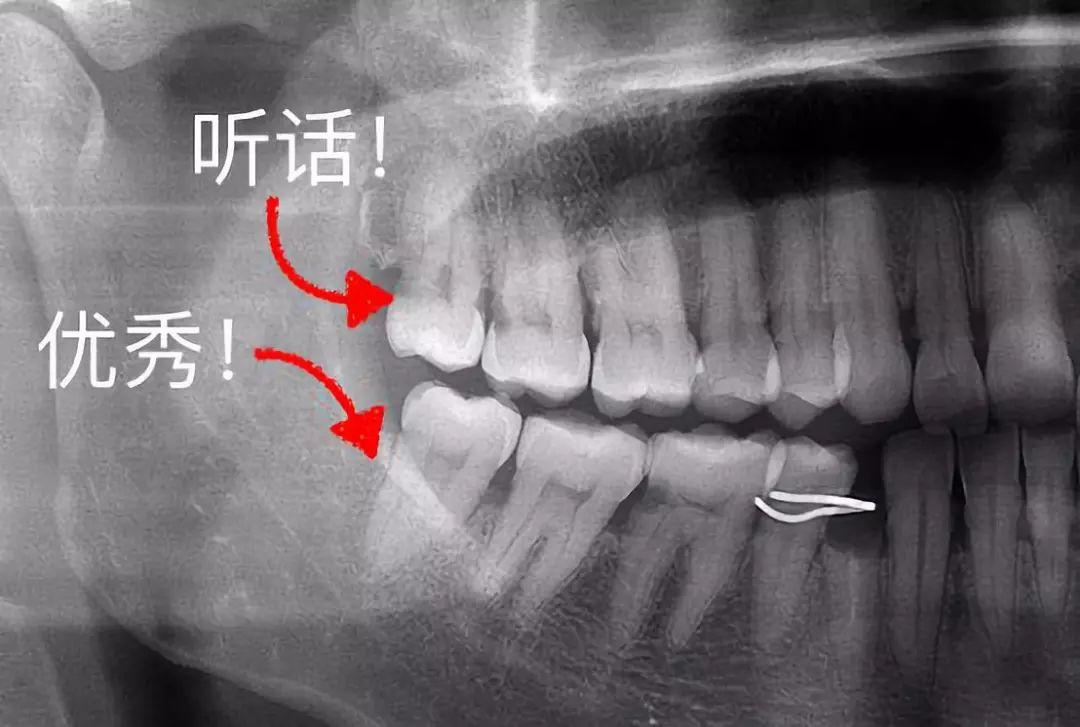

智齒前方的牙齒已經(jīng)出現(xiàn)蛀洞

▼

▍來(lái)源:何劍亮醫(yī)生

3、這些「聽(tīng)話(huà)」的智齒不用拔

有一些特別乖的智齒,整整齊齊長(zhǎng)出來(lái),上下可以咬合,也沒(méi)有什么蛀牙,平時(shí)都能刷干凈。那么,這種、聽(tīng)話(huà)的智齒完全可以留下,成為咀嚼食物的工具。

整齊、正位萌出的智齒